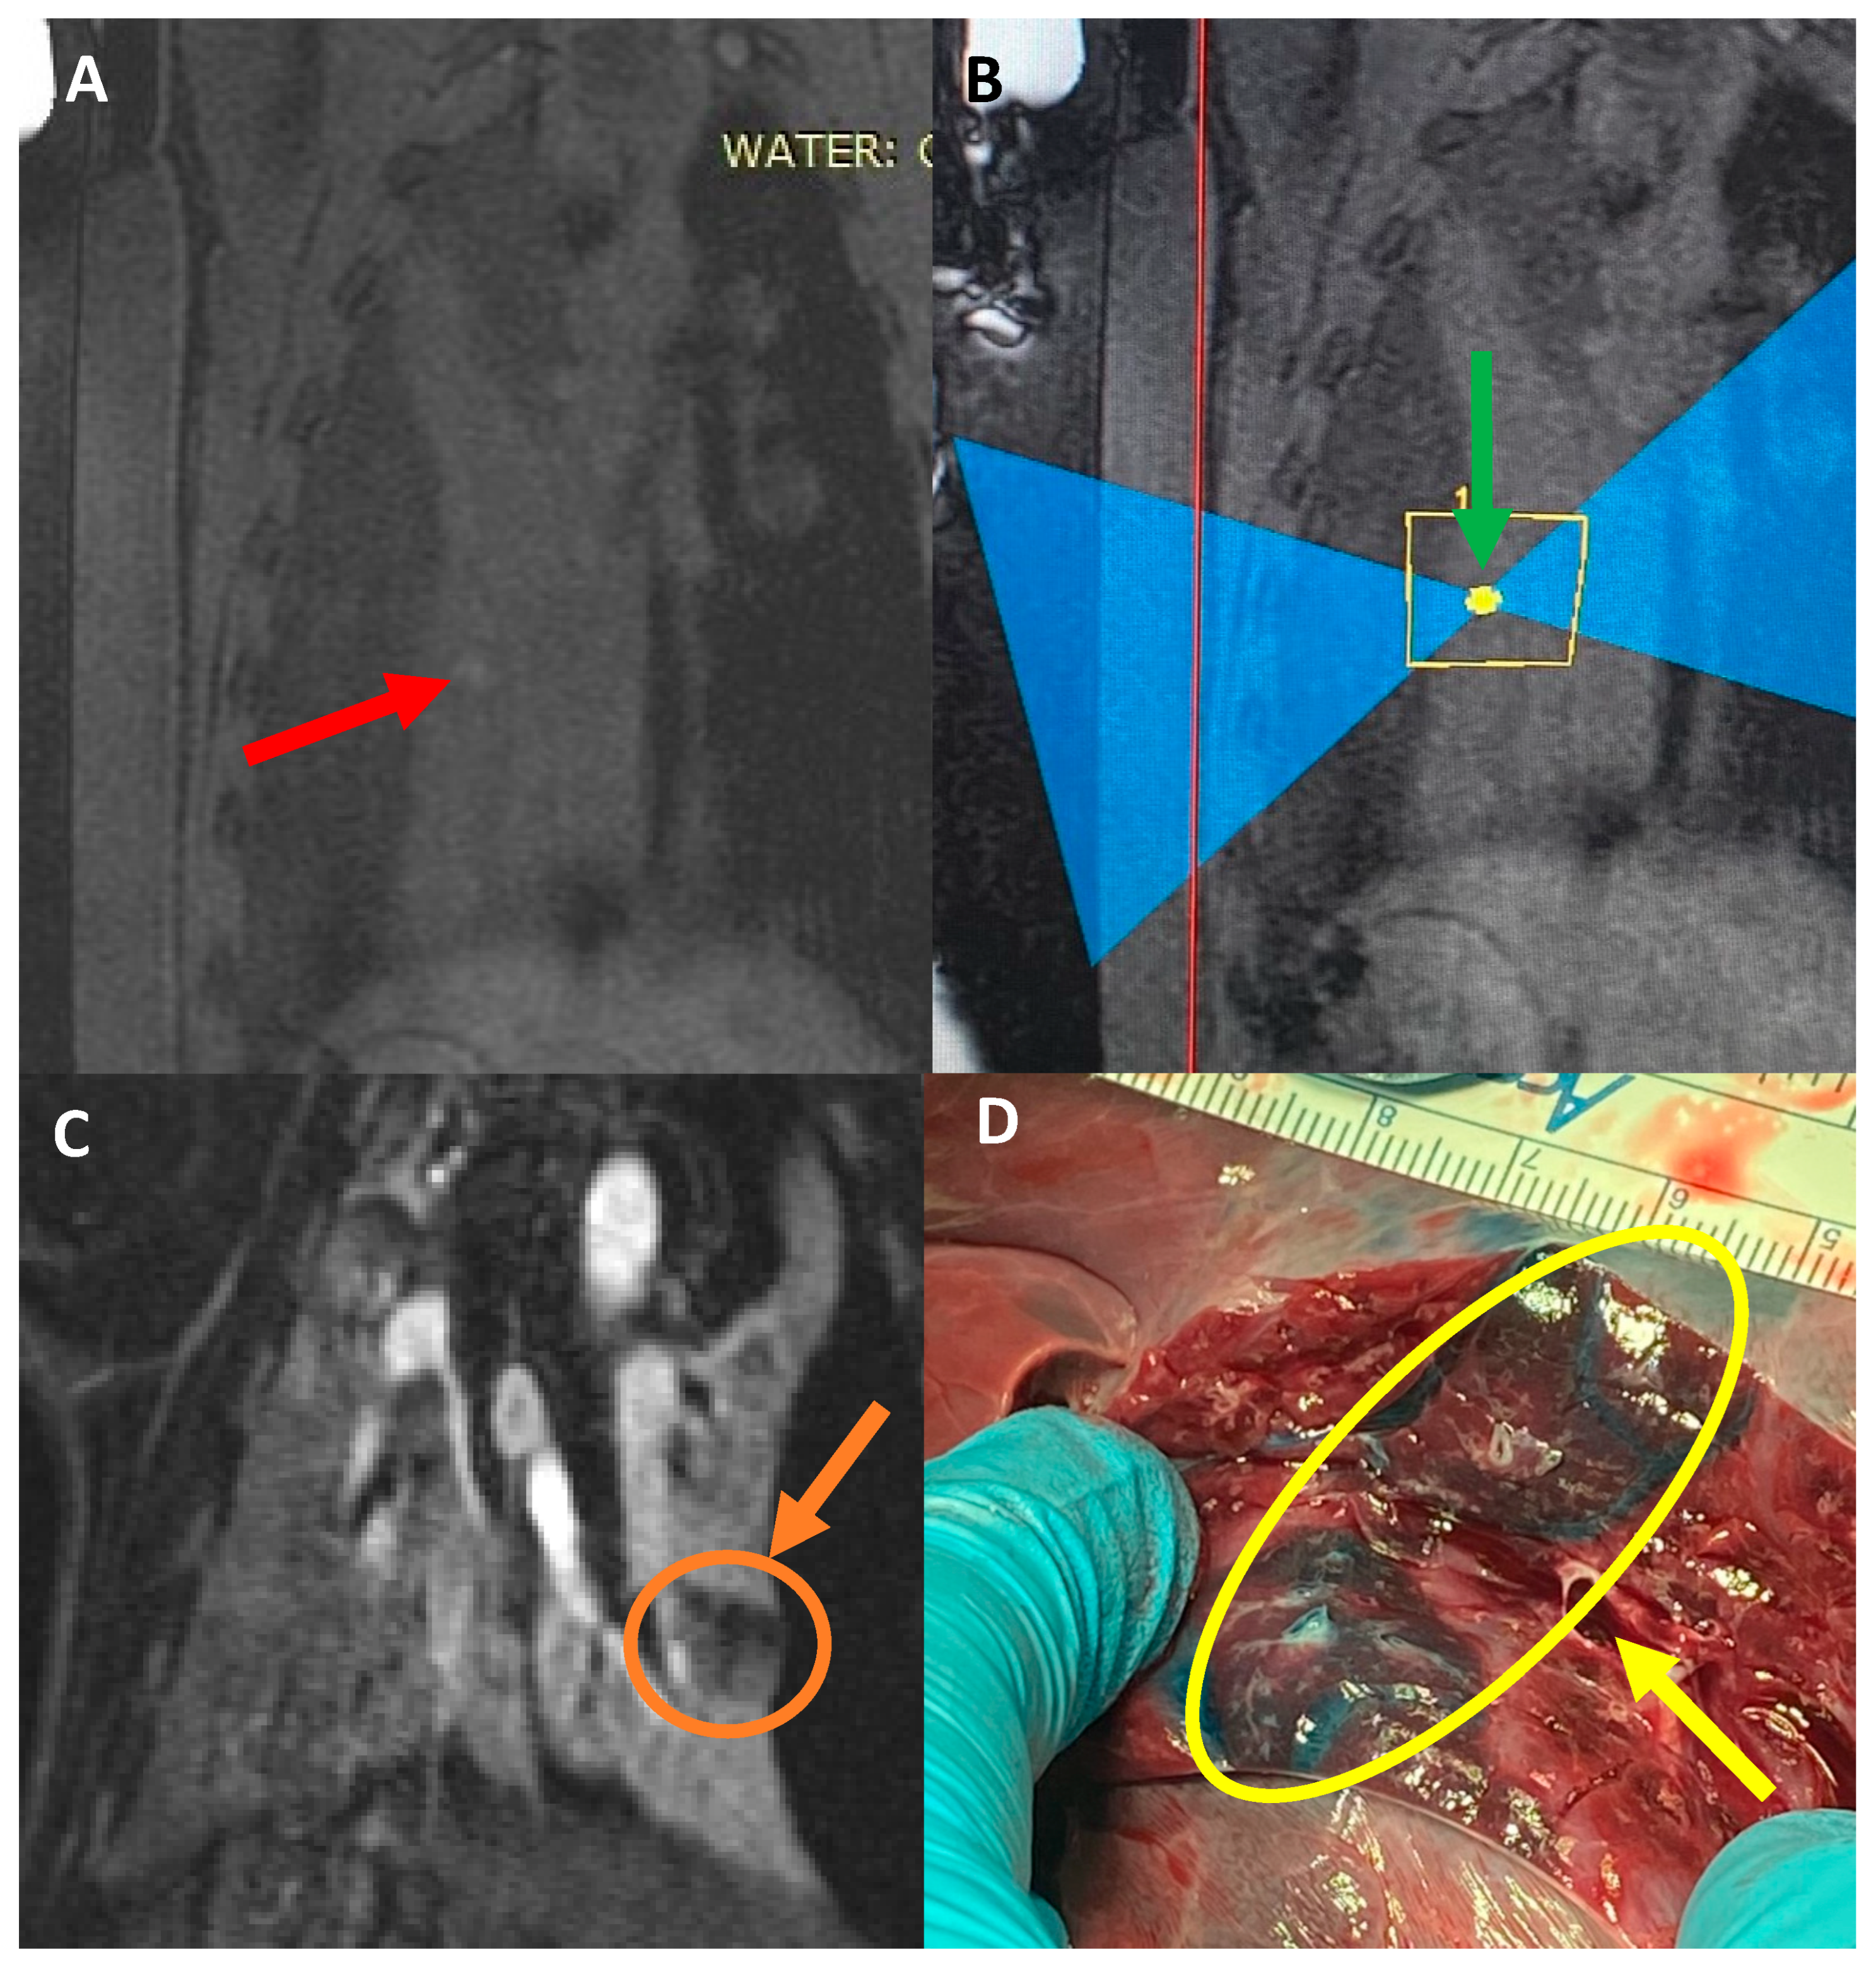

In pig #2, the aim was to study the health effects following MRgFUS with multiple (six) doses of a higher power delivered at six different locations but using only two intercostal/skin areas as entry points. Following the six treatments with MRgFUS at 350 Watts for 20 s each, mild burn marks were visible on the skin at the FUS beam entry points. The pig recovered successfully from the anesthesia. Mild wheezing was noticeable in the week-long post-treatment follow-up. After one week, the pig was scanned using MRI and had hyper-intense regions in the left lung that corresponded with the treatment locations (an example is shown Figure 2). The pig was then euthanized and examined utilizing gross histology. At the locations of the MRgFUS treatment, there were dense fibrotic tissues with white discoloration, indicating successful lung parenchyma ablation (Figure 3A). There was no damage observed on the pericardium or heart.

Furthermore, all of the subsequent pigs showed successful ablations in the one-week post-treatment MRI and in their gross histology, with the tissue corresponding to the targeted areas having a hard and fibrotic consistency upon necropsy (Figure 3B). The lung tissue biopsies of the healthy and targeted tissue were examined using histology and confirmed that the FUS-targeted tissues presented a denser fibrotic consistency instead of normal alveolar structures and red blood cells (Figure 4). Pig #9 was unique in that there was a wedge-shaped lesion in the upper right lung. This lesion may have been due to reflection of the MRgFUS beam off the opposing ribcage, as the largest section of the wedge was closest to the ribcage. All of the pigs remained healthy during the post-treatment follow-up week, with no noticeable health complications.

Pigs #10–11 received a liquid mixture of Vitamin E, Evans blue, and food dye in the collapsed lung parenchyma. As planned, the Vitamin E provided a hyper-intense target in the pre-treatment lung MR images (Figure 5A), and each pig received three ablations at 350 Watts for 20 s, each targeting this specific spot (Figure 5B). The ablations were visible on the post-treatment MRI with and without gadolinium contrast, but the absence of perfusion in the ablated areas was noted in the post-gadolinium MR images (Figure 5C), showing the damage of the FUS on the targeted area of the collapsed lung. Upon necropsy, there was no collateral damage noted on the skin, subcutaneous tissue, or muscle. The target sites were highly visible as a blue stain, with an area of ablation in the center, which appeared as a firm, coned area (Figure 5D).

Figure 5. (A) Coronal image of pig #11 pre-treatment. Red arrow points toward the location that the Vitamin E mixture was injected into, which shows a hyperintense region. (B) Sagittal image during treatment. Green arrow points toward the targeted location. (C) Coronal T1 weighted MR image, post-contrast showing the hypo-perfused ablated area. Orange arrow depicts the size of the ablation. (D) Necropsy of the targeted area. Yellow arrow depicts the target area generated with the dye mixture. The ablated tissue was firm and directly in the targeted area.